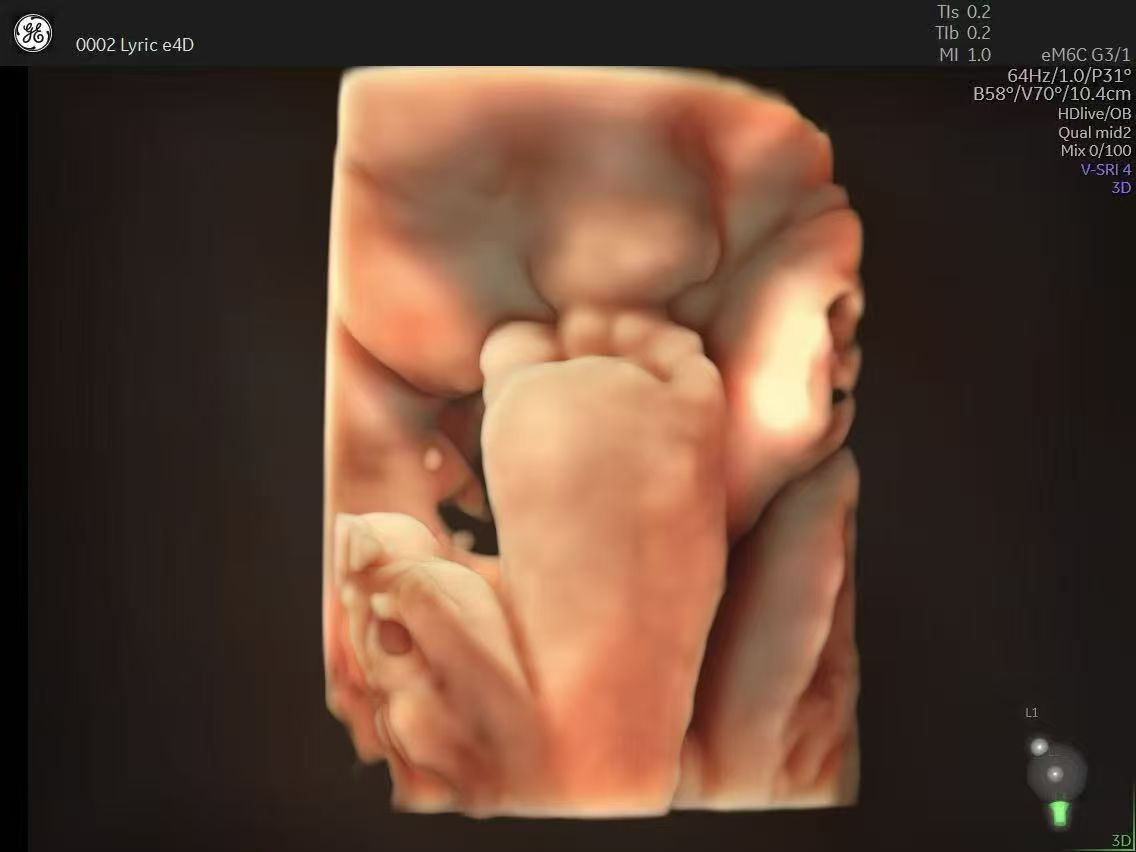

Lyric天琴平台加持,空间分辨率与对比度双重升级,胎儿细微动作、脏器边界清晰可辨。

自动生成胎儿宫内动态视频,记录微笑、皱眉等可爱瞬间,为准父母留下珍贵纪念。

在传统超声设备上难以清晰显示的手指、面部细微表情等结构,如今在E22的扫描下都一目了然。其高帧率技术让胎儿在宫内的实时动作(如打哈欠、吸吮)更加连贯自然,为准父母提供了更加珍贵的动态记录。